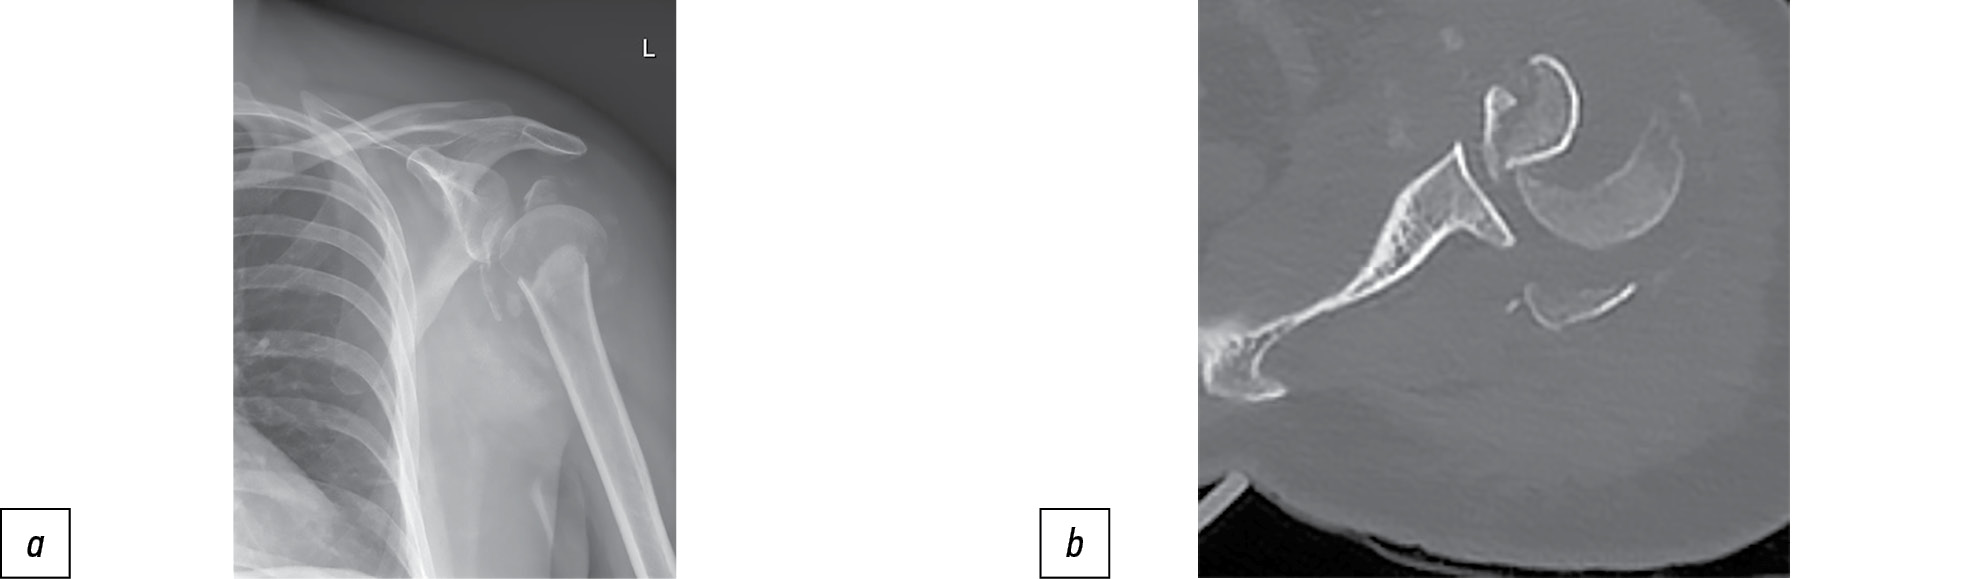

- наличие 2–3–4-фрагментного перелома по классификации Neer со смещением, сопровождающегося дефицитом кости, т.е. при мультиспиральной компьютерной томографии (МСКТ) головка плечевой кости визуализируется в виде «серпа», и бугорковая зона головки разрушена (рис. 1);

Рис. 1. Четырёхфрагментный перелом по Neer с дефицитом кости.

Примечание. a — рентгенограмма левого плечевого сустава, b — мультиспиральная компьютерная томограмма, аксиальный срез — головка визуализируется в виде серпа, т.е. сохранена только субхондральная кость.

Fig. 1. Four-fragment Neer fracture with bone deficiency.

Note. a — radiograph of the left shoulder joint. b — MSCT axial section — the head is visualized in the form of a sickle, i.e. only the subchondral bone was preserved.